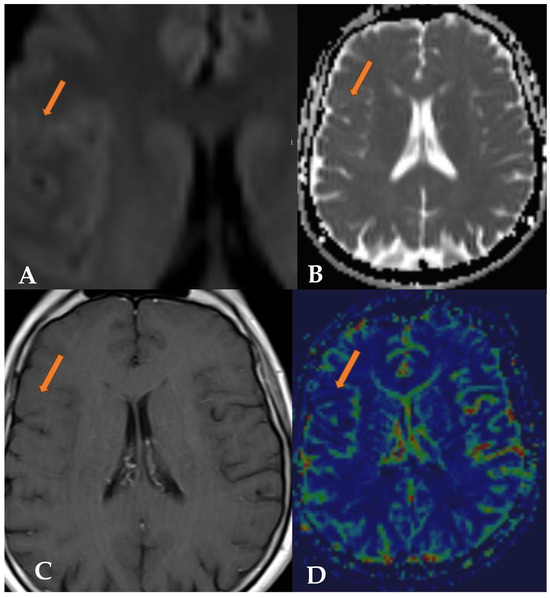

2.1. Case 1